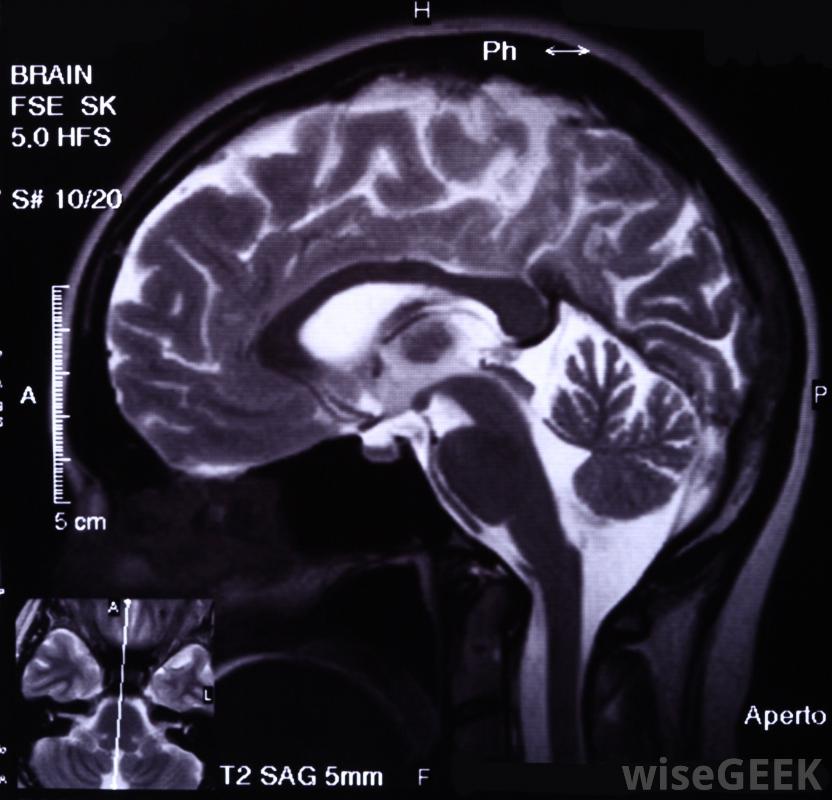

脑瘤可能导致患者思维模糊和思维混乱外科手术是治疗多种癌症的首选治疗方法之一,尤其是与药物或放射治疗结合使用时,外科手术通常能极大地改善病人的预后,发生在脑部的肿瘤往往更难用手术来治疗,因为大脑的功能既脆弱又重要MRIs和其他脑成像技术可以用来定位和测量肿瘤。恶性肿瘤可以在大脑的许多不同区域及其支持结构中形成大脑的外围区域,例如靠近神经的区域,将感觉输入输入大脑,更容易成为外科治疗的好选择生长在负责基本运动功能的大脑区域或位于大脑结构深处的肿瘤不太适合手术用化疗缩小不能手术的脑瘤。在某些情况下,即使是扩散很慢的肿瘤,如果它形成于大脑中特别敏感或关键的部位,也可能被归类为恶性肿瘤位于大脑这一部分的肿瘤很可能是一种无法手术治疗的脑癌。然而,尽管无法通过手术治疗,但并非所有这些癌症都会立即危及生命。

这很困难对生长在大脑中处理基本运动功能的区域的肿瘤进行手术。第二种情况是肿瘤被认为是不可手术的脑癌取决于肿瘤的扩散程度在脑内。一个边缘清晰的肿瘤通常比一个在大脑中广泛分布的组织卷须的肿瘤更适合手术切除。这种肿瘤不适合外科手术切除,因为手术不太可能切除所有的恶性组织,而且手术是在这样一个扩散的肿块上进行的细胞可能需要切除大量的脑组织,结果很危险

脑癌在检测时的扩散程度是决定手术是否可行的一个关键因素,不能手术的脑癌也可能是一个结果指病人整体健康状况不佳。身体虚弱、免疫系统受损或患有其他疾病的病人,在手术对身体造成的压力下,存活的可能性较小。在这种情况下,即使能在健康的病人身上进行手术治疗,肿瘤也可被视为不可手术的脑癌位于大脑外围的肿瘤是外科治疗的好选择src="1234562"/>恶性肿瘤可以在大脑的许多不同区域及其支持结构中形成。